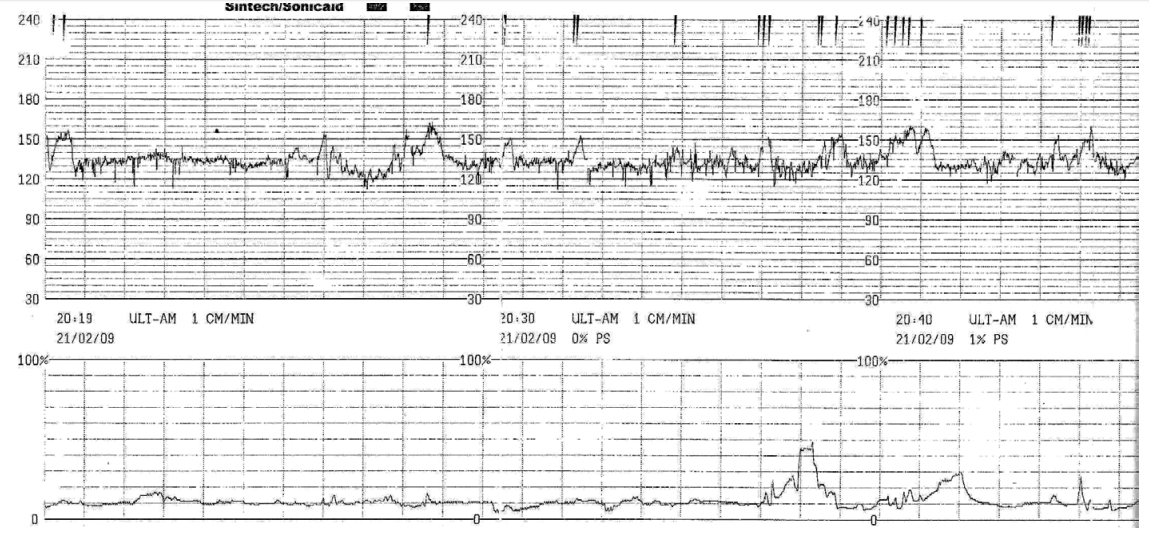

Gestante de risco habitual, com 3 partos vaginais prévios, encontra-se com

40 semanas, em trabalho de parto espontâneo, com 8 cm de dilatação, bolsa íntegra e evolução dentro do esperado. Durante a ausculta intermitente dos batimentos cardíacos fetais foi observada queda dos batimentos cardíacos fetais, sendo

realizada a cardiotocografia abaixo.

Diante da história e do traçado, assinale a alternativa que corresponde à conduta

correta.